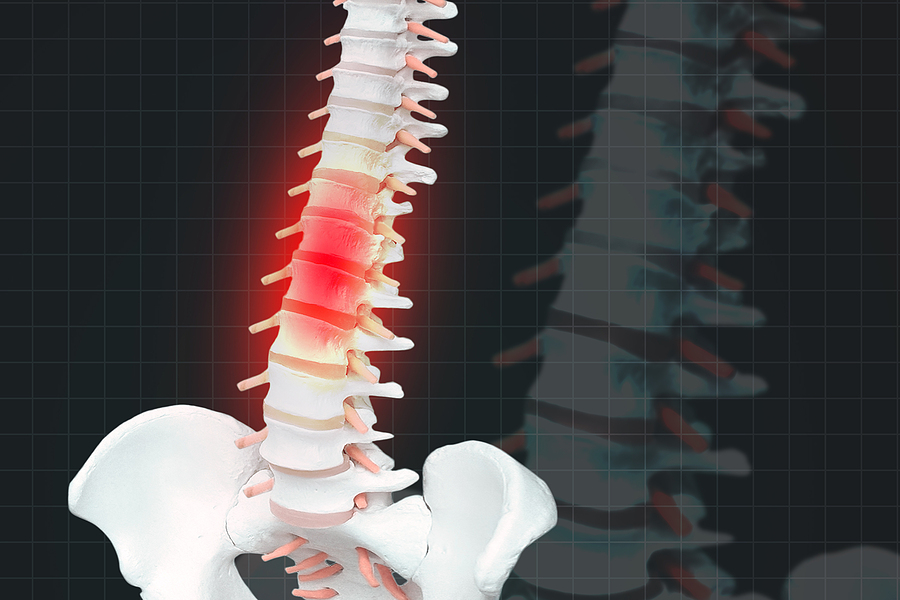

Spinal injuries can occur because of many different types of accidents, including motor vehicle accidents, slip and fall accidents, because of defective products, and even due to medical malpractice. Spinal injuries can range from moderate to severe depending on the cause of the injury and the location in which you were injured. Most spinal injuries are not “mild” since an injury to the spinal cord or surrounding area almost always causes severe pain and disruption to your life.

A spinal injury that occurs lower on the spinal column is more likely to be classified as incomplete, while an injury that occurs higher up is more likely to be considered complete. A complete spinal injury means that the spinal cord has been severed completely and the victim has fully lost the ability to convey messages to or from the brain. An incomplete injury means that ability is only partially lost.